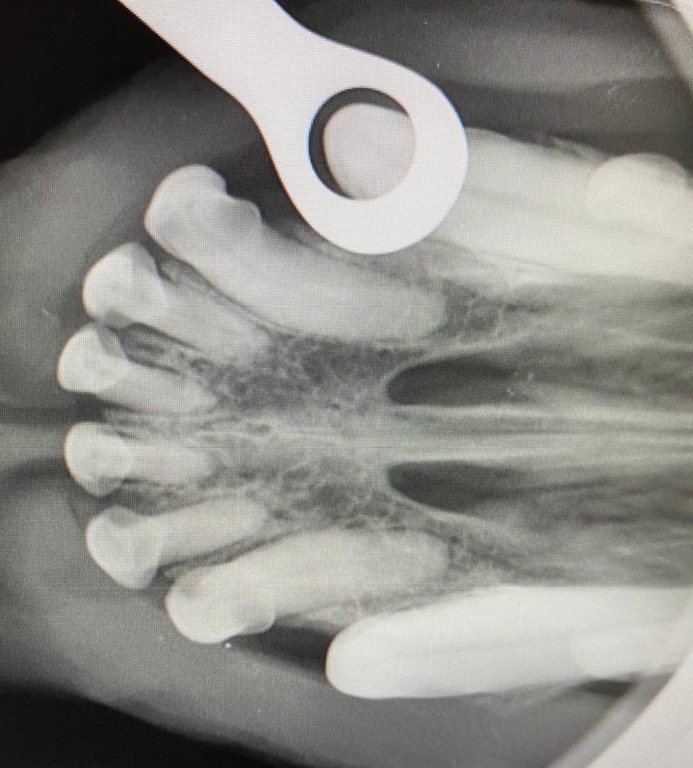

- das Dentalröntgen zur Abklärung dieser Patienten

Die Voraussetzung für eine gute Therapie dieser Tiere, ist eine gute und genaue Diagnostik. Hierfür kann man auf das intraorale Dentalröntgen nicht verzichten. Die meisten krankhaften Veränderungen befinden sich im äußerlich nicht sichtbaren Bereich der Zahnwurzel und des Zahnhalses und können nur durch bildgebende Verfahren sichtbar gemacht werden.